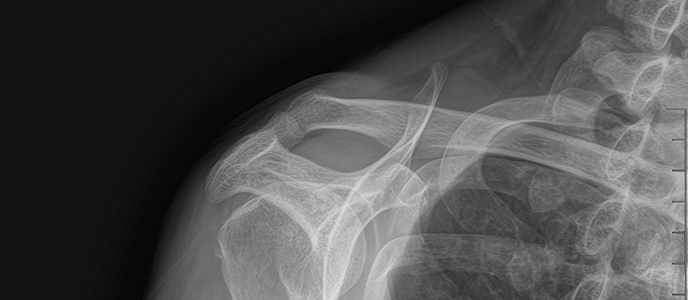

치료 증상 자고 나서 팔을 들기 힘들 정도의 심한 어깨 통증

나이/성별 45세 / 남성

치료 내용 석회쇄석흡인술 후 호전

치료 기간 2024-09-12 ~ 2024-12-18

치료 증상 잘 때도 아파서 깸 , 팔 들기 힘듦

나이/성별 50세 / 여성

치료 기간 2025-02-22 ~ 2025-02-22

※ 해당 사진은 수정없는 실제 치료사진입니다. 환자의 치료결과는 환자의 상태, 치료방법 등에 따라 차이가 발생할 수 있습니다.